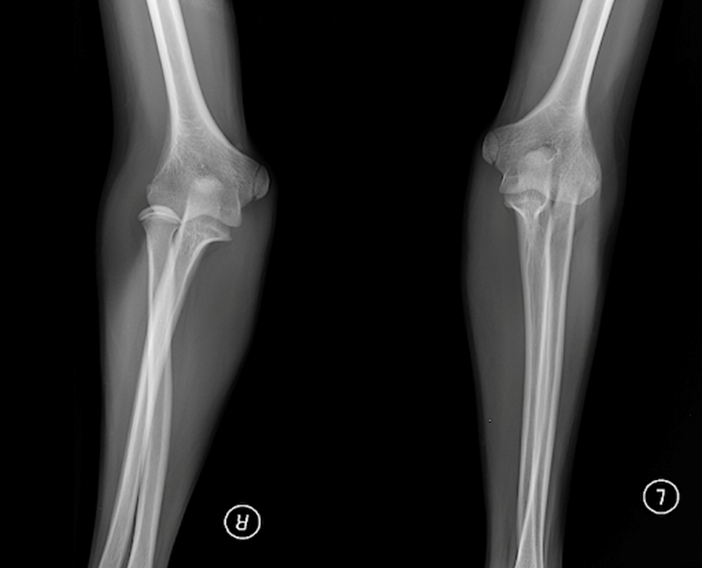

ПЕРЕЛОМ ЯКОЇ КІСТКИ І ЯКОЇ ЇЇ ЧАСТИНИ ВИ БАЧИТЕ НА РИСУНКУ?

варіанти відповідей

ДИСТАЛЬНОГО ДІАФІЗА

HUMERUS

ULNA

RADIUS

ПРОКСИМАЛЬНОГО ЕПІФІЗА

ДИСТАЛЬНОГО ЕПІФІЗА

ДІАФІЗА

МЕТАФІЗА